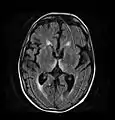

Wernicke-Korsakoff syndrome in people with chronic alcohol use particularly is associated with atrophy/infarction of specific regions of the brain, especially the mammillary bodies. Other regions include the anterior region of the thalamus (accounting for amnesic symptoms), the medial dorsal thalamus, the basal forebrain, the median and dorsal raphe nuclei,[18] and the cerebellum.[19]

Brain atrophy associated with WKS occurs in the following regions of the brain:

1. the mammillary bodies,

2. the thalamus,

3. the periaqueductal grey,

4. the walls of the 3rd ventricle,

5. the floor of the 4th ventricle,

6. the cerebellum, and

7. the frontal lobe.

In addition to the damage seen in these areas there have been reports of damage to cortex, although it was noted that this may be due to the direct toxic effects of alcohol as opposed to thiamine deficiency that has been attributed as the underlying cause of Wernicke-Korsakoff Syndrome.[25]

The amnesia that is associated with this syndrome is a result of the atrophy in the structures of the diencephalon (the thalamus, hypothalamus and mammillary bodies), and is similar to amnesia that is presented as a result of other cases of damage to the medial temporal lobe.[26] It has been argued that the memory impairments can occur as a result of damage along any part of the mammillo-thalamic tract, which explains how WKS can develop in patients with damage exclusively to either the thalamus or the mammillary bodies.[25]

Frequently, secondary to thiamine deficiency and subsequent cytotoxic edema in Wernicke encephalopathy, patients will have marked degeneration of the mammillary bodies. Thiamine (vitamin B1) is an essential coenzyme in carbohydrate metabolism and is also a regulator of osmotic gradient. Its deficiency may cause swelling of the intracellular space and local disruption of the blood-brain barrier. Brain tissue is very sensitive to changes in electrolytes and pressure and edema can be cytotoxic. In Wernicke this occurs specifically in the mammillary bodies, medial thalami, tectal plate, and periaqueductal areas. People with the condition may also exhibit a dislike for sunlight and so may wish to stay indoors with the lights off. The mechanism of this degeneration is unknown, but it supports the current neurological theory that the mammillary bodies play a role in various "memory circuits" within the brain. An example of a memory circuit is the Papez circuit.